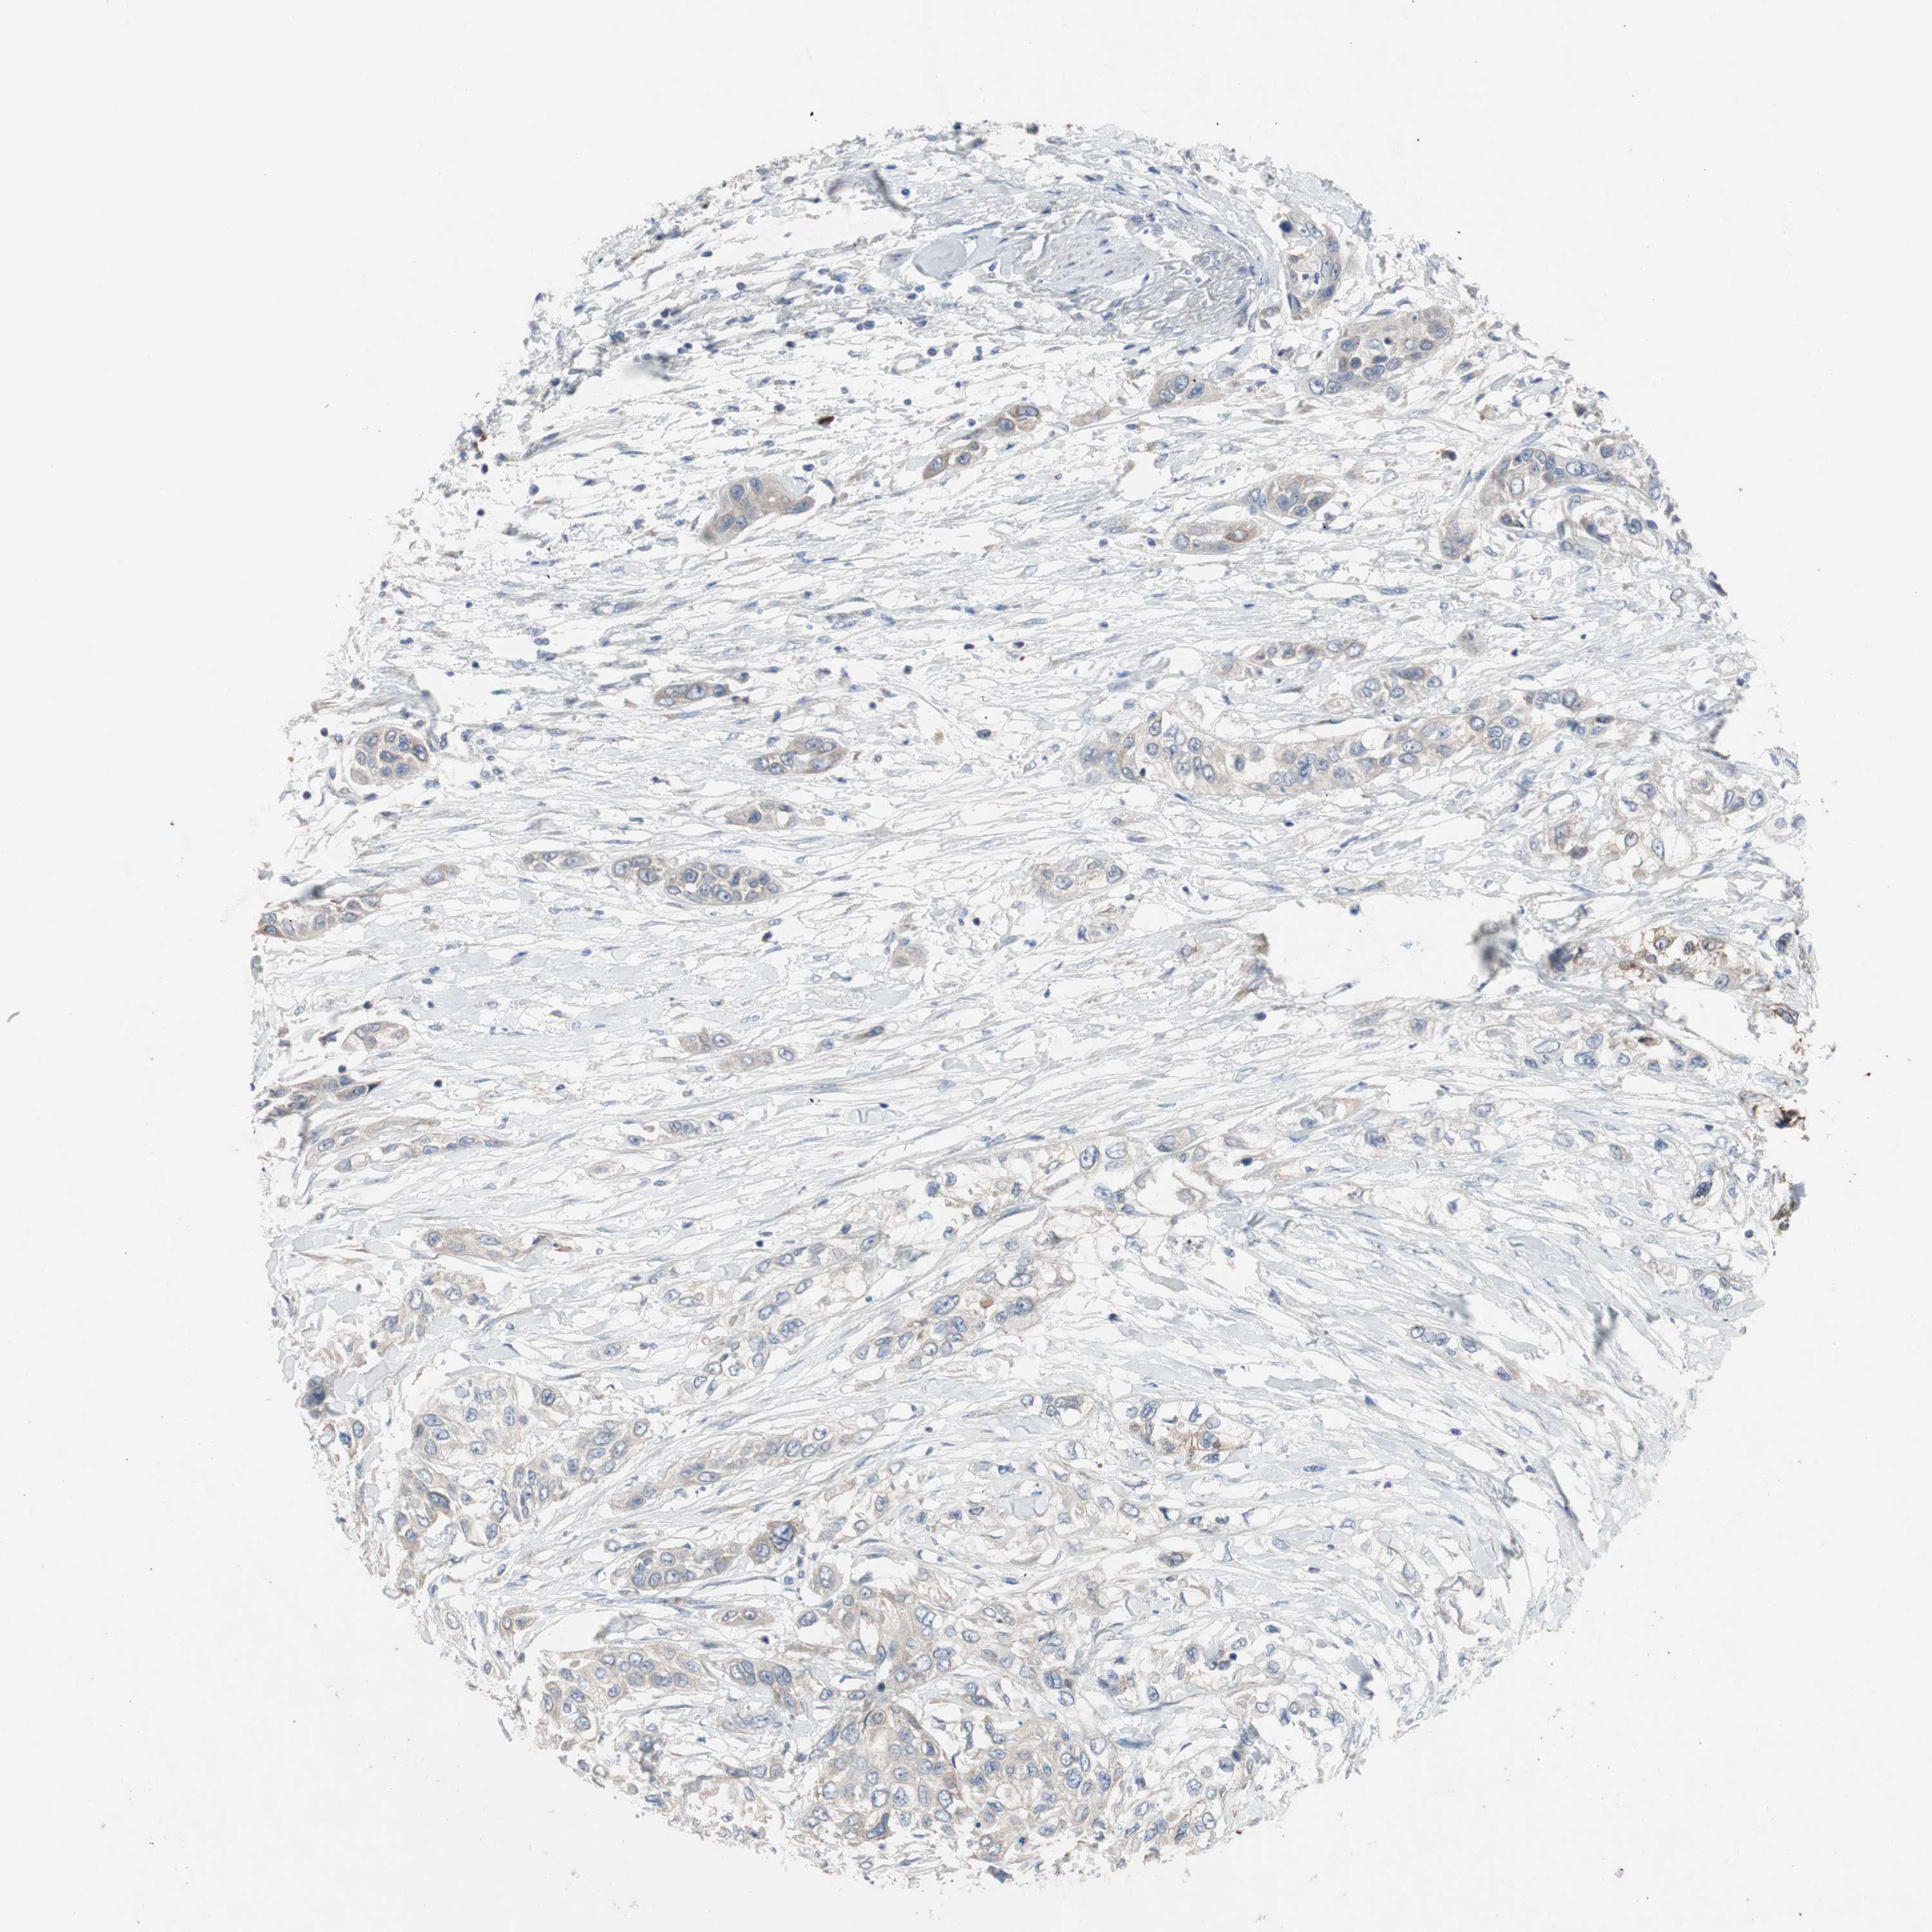

PANCREATIC CANCER - Protein expressioni

A mouse-over function shows sample information and annotation data. Click on an image to view it in a full screen mode. Samples can be filtered based on level of antibody staining by selecting one or several of the following categories: high, medium, low and not detected. The assay and annotation is described here.

Note that samples used for immunohistochemistry by the Human Protein Atlas do not correspond to samples in the TCGA dataset.

Antibody stainingi

Antibody staining in the annotated cell types in the current human tissue is reported as not detected, low, medium, or high, based on conventional immunohistochemistry profiling in selected tissues. This score is based on the combination of the staining intensity and fraction of stained cells.

Each image is clickable and will lead to virtual microscopy that enables deeper exploration of all samples and also displays staining intensity scores, fraction scores and subcellular localization as well as patient and tissue information for each sample.

Antibody HPA009295

Staining

High

Medium

Low

Not detected

Intensity

Strong

Moderate

Weak

Negative

Quantity

>75%

75%-25%

<25%

None

Location

Nuclear

Cytoplasmic/membranous

Cytoplasmic/membranous,nuclear

Adenocarcinoma, NOS